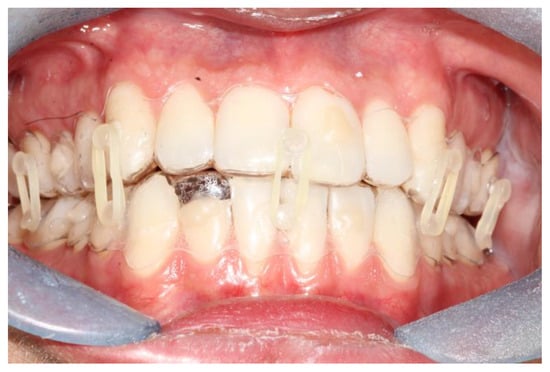

The fixation strength of the intermaxillary fixation was considered adequate in both cases (Figure 5 and Figure 6).

Occlusion and periodontal tissue were within normal clinical ranges after the treatment (Figure 6).

Only in the first patient, where the splint margin covered the attached gingiva, was some periodontal inflammation noted (Figure 7).

Figure 5. Intraoral view of patient 2 during the treatment; is it possible to note the slight problem with oral hygiene, which is nonetheless completely acceptable.

Figure 6. Intraoral view of patient 1 during the treatment; is it possible to note the slight problem with oral hygiene, which is nonetheless completely acceptable.